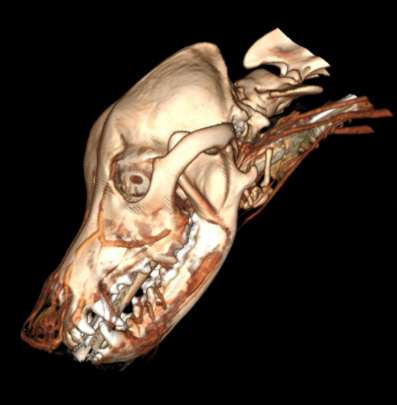

cranio canino imagem de tomografia

Tanto a TC quanto a RM utilizam tecnologia de alta precisão para reconstruir imagens da anatomia em três dimensões.

Quando escolher Tomografia Computadorizada (TC)?

A TC utiliza radiação (como o raio-X) e é excelente para diferenciar estruturas com densidades distintas, como osso, ar e tecido.

O exame é rápido, geralmente de 10 a 20 minutos, e muitas vezes pode ser feito apenas com sedação.

É muito útil em:

• Traumas agudos de cabeça

• Fraturas de coluna

• Neoplasias ósseas

• Tumores nasais

• Otite média/externa

• Casos de emergência pela rapideZ

A TC usa radiação (raios X – como as radiografias), sendo melhor para diferenciar tecidos com densidades distintas, como osso, ar e água (tecido).

A força da TC está no uso em traumas cranianos agudos, fraturas vertebrais, neoplasias ósseas, alguns tumores nasais e otite média/externa.

A TC é frequentemente utilizada em emergências devido à disponibilidade e ao tempo curto de escaneamento.